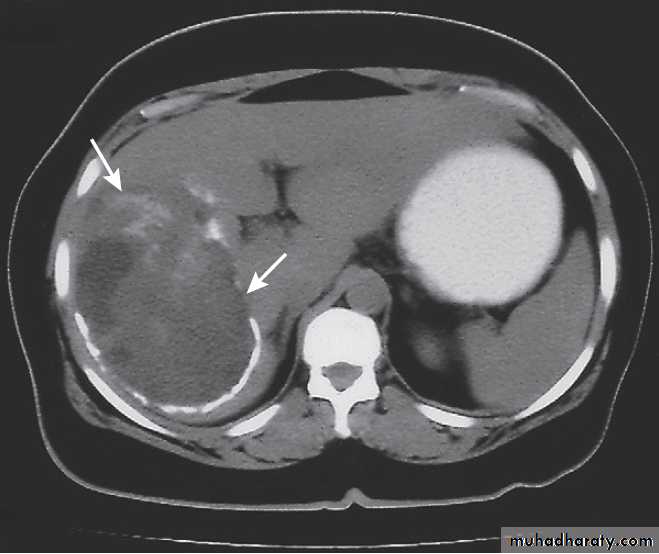

Hydatid cyst of the liver on CT (arrows).